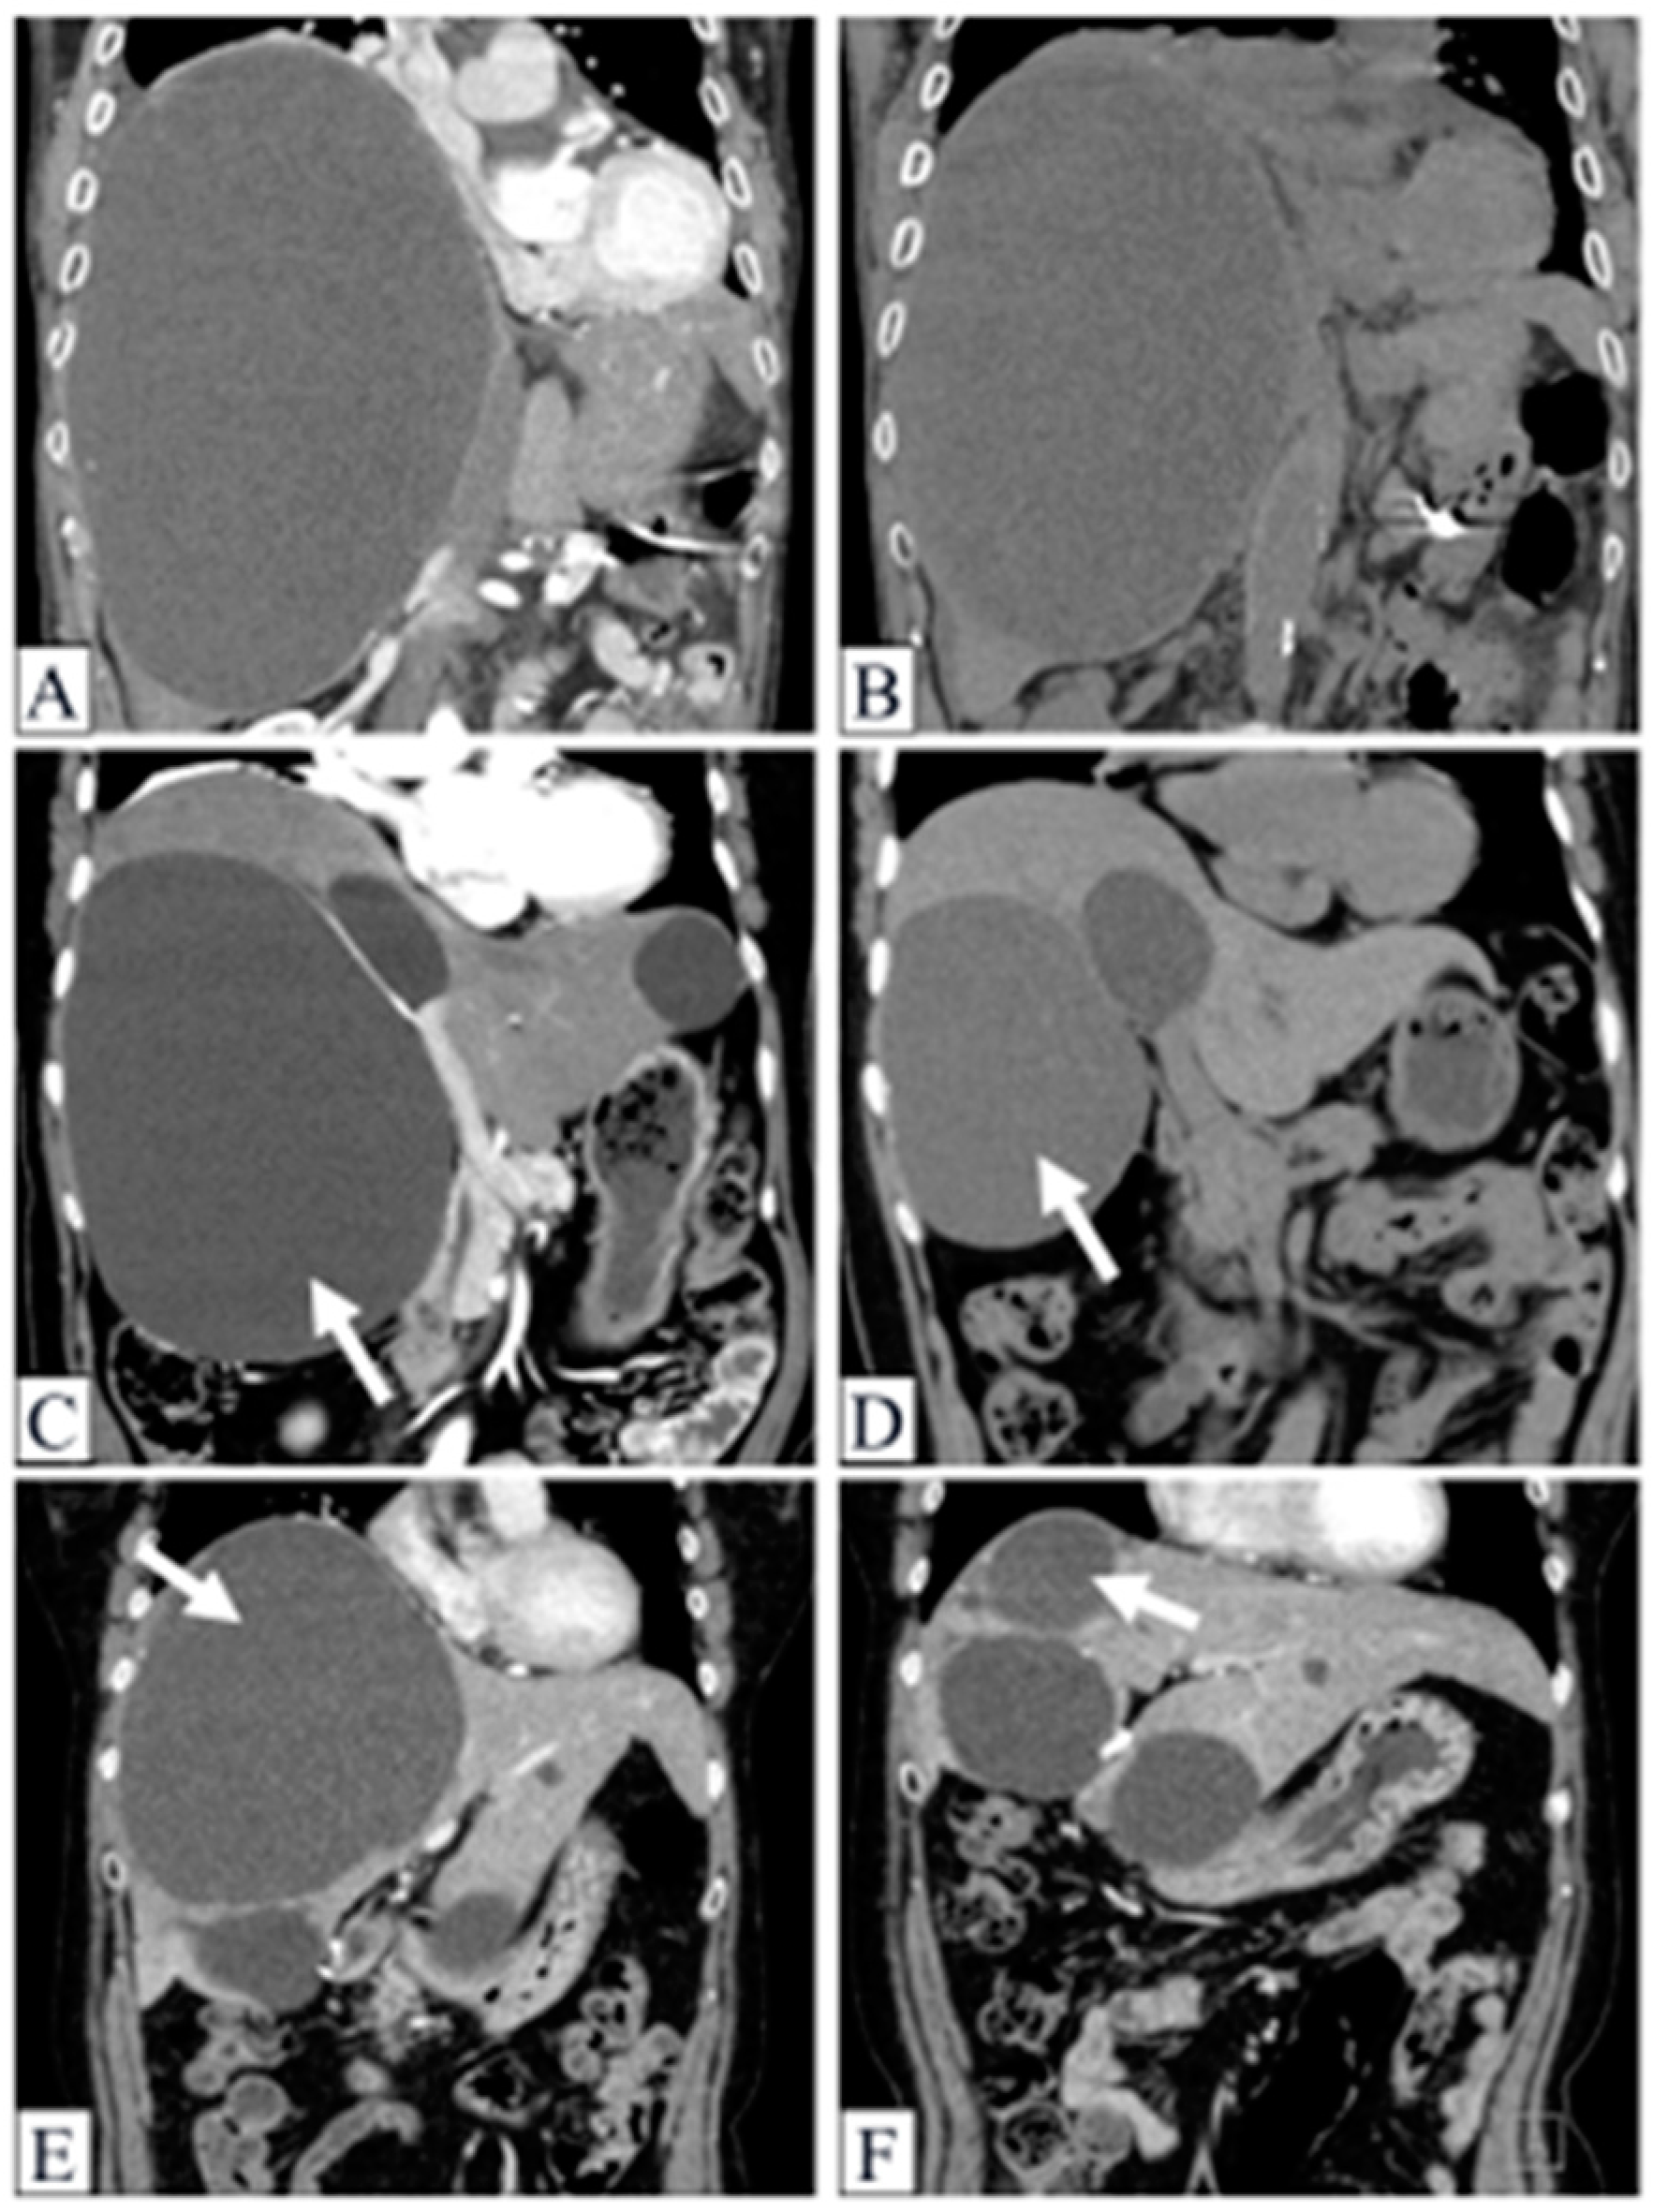

2.6. Demonstrable Cases

2.6.1. Case 1

2.6.2. Case 2

2.6.3. Case 3